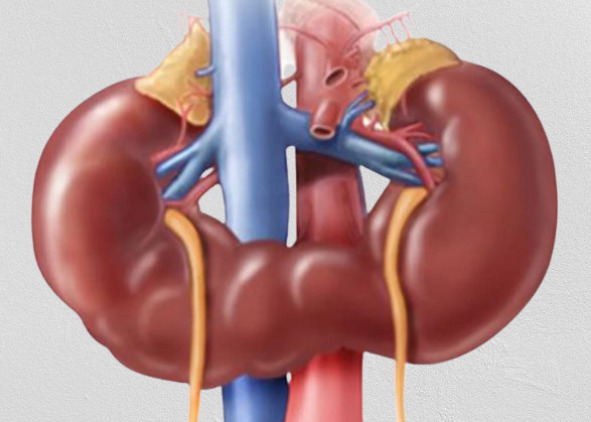

(Слева) Подковообразная почка. Нижние полюсы почек медиально отклонены, по срединной линии - перешеек. Питающие артерии, как правило, отходят от аорты или подвздошных артерий.

(Справа) Переднемедиальная ориентация лоханок может указывать на подковообразную почку. Тщательное сканирование по срединной линии позволяет даже во II триместре кпереди от аорты обнаружить паренхиматозную перемычку между почками.